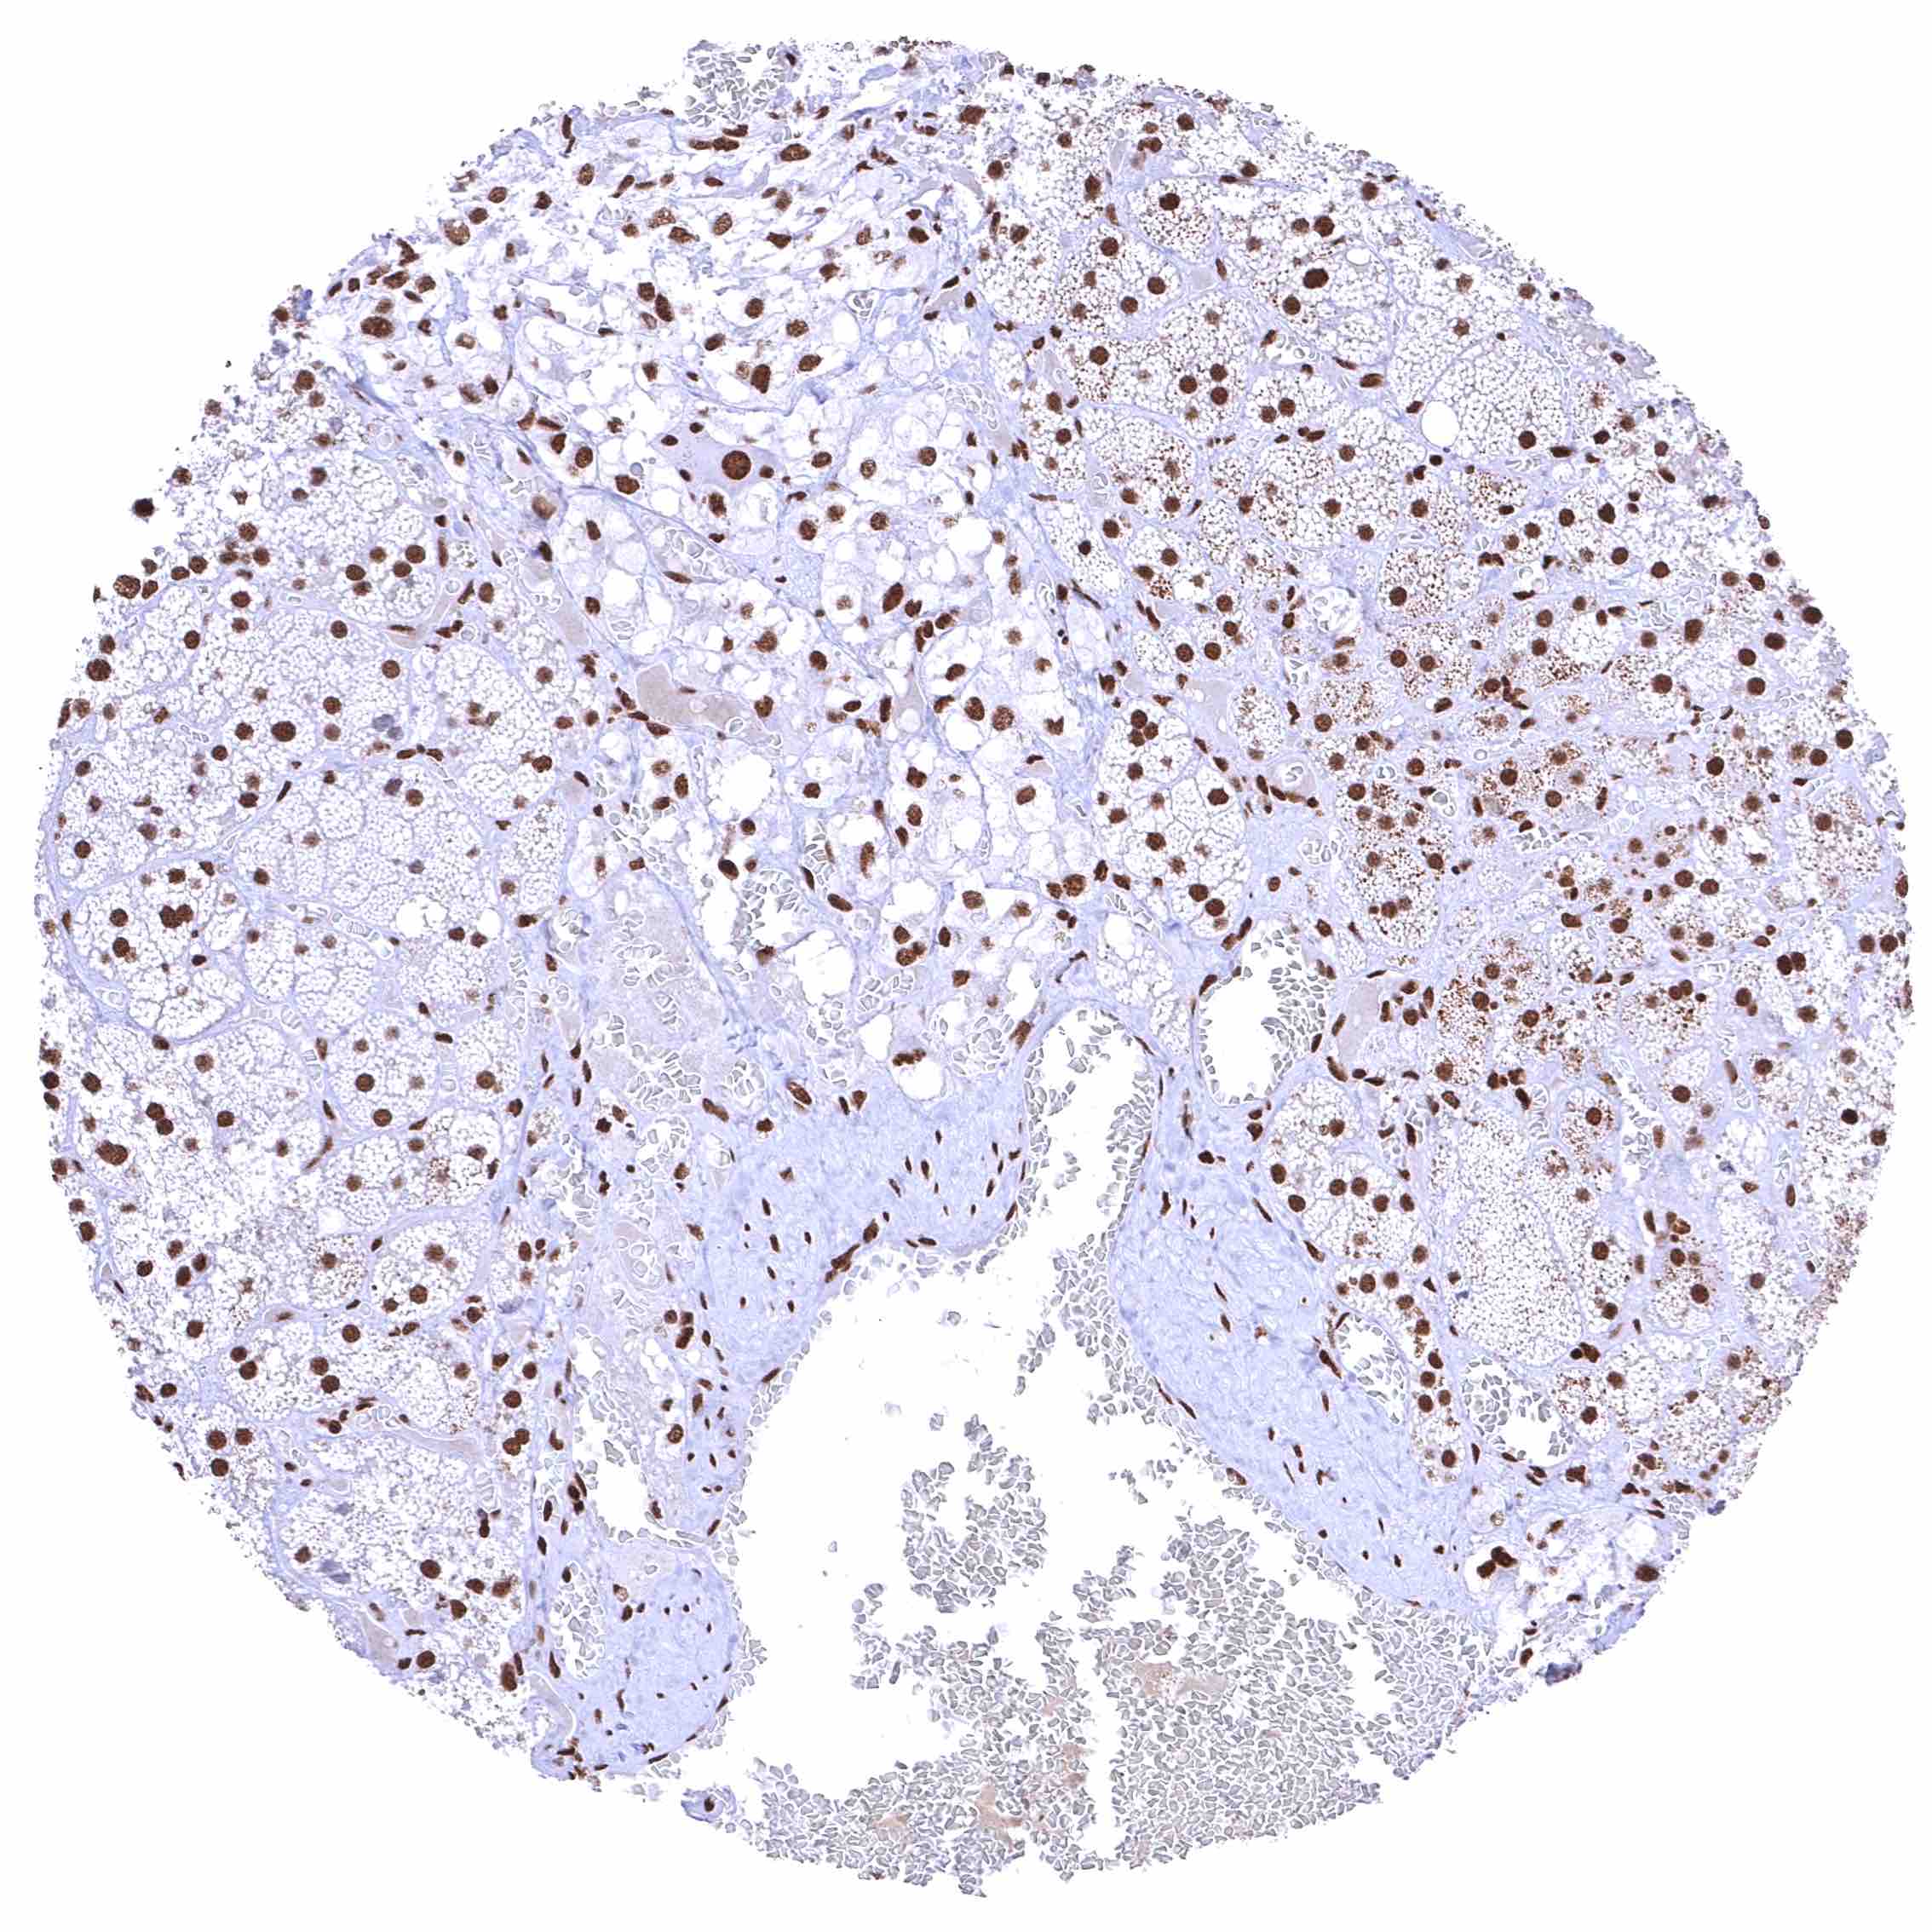

BRD4 antibody [HMV4275] HistoMAX™

Lung